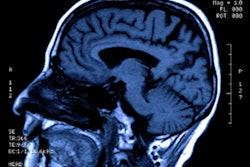

MRI shows eight particular neurologic findings in patients with severe COVID-19, according to a study published June 16 in Radiology.

The study results could help clinicians better recognize the effects of the disease, wrote a team led by Dr. Stéphane Kremer of Hôpital de Hautepierre in Strasbourg, France.

The study included 37 patients evaluated between March 23 and April 27 at 16 hospitals who had the following clinical findings: positive nasal or lower respiratory tract reverse transcription polymerase chain reaction (RT-PCR) assays, severe COVID-19 infection that required hospitalization and oxygen, neurologic manifestations, and abnormal brain MRI scans.

The group outlined eight neurologic patterns in patients with severe COVID-19 and abnormal MR images:

- Signal abnormalities in the medial temporal lobe (43%)

- Nonconfluent multifocal white matter hyperintense lesions on fluid-attenuated inversion recovery (FLAIR) and diffusion MRI sequences, with variable enhancement and associated hemorrhagic lesions (30%)

- Extensive white-matter microhemorrhages (24%)

- Extensive and confluent supratentorial white-matter FLAIR hyperintensities (11%)

- FLAIR and diffusion ovoid hyperintense lesions located in the central splenium of the corpus callosum (5%)

- Nonconfluent multifocal white matter hyperintense lesions on FLAIR/diffusion, with variable enhancement (5%)

- Acute necrotizing encephalopathy (5%)

- FLAIR or diffusion hyperintense lesions involving both middle cerebellar peduncles (5%)

The study results underscore the importance of following patients with these neurological findings on MRI, according to the authors.

"Imaging and neurological follow up has to be undertaken in order to evaluate the prognosis of these patients," they concluded.